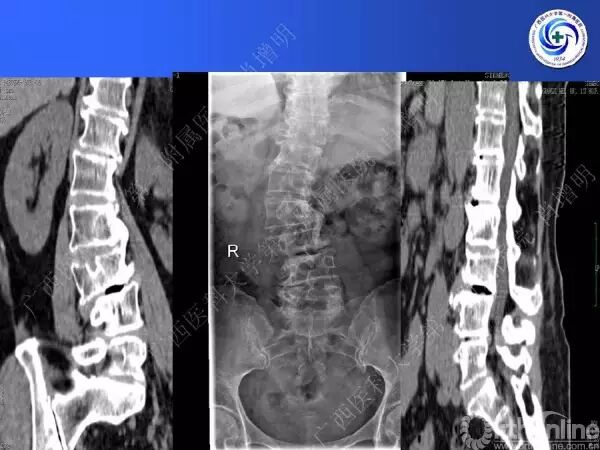

退变性脊柱侧凸是由于椎间盘退变后继发小关节退变,椎管和神经根管容积变化以及脊柱失稳,畸形等病理改变,以疼痛和神经压迫症状为主要表现的常见疾病。

退变性脊柱侧凸多发于50岁以上的中老年群体,是现代常见的老年疾病。多年来,针对该病的临床研究一直没有停步,广西医科大学第一附属医院肖增明教授细致地介绍了该病的诊疗进展。